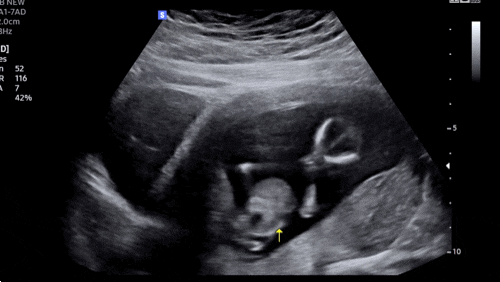

[임신 12주차]증상,드디어 첫 정밀초음파, 성별❣️

엘디와 함께한지 벌써 12주 째! 안정기 시작으로 불리우는 주수이고 나는 드디어!!! 크녹산과 이별했다~~~ ...